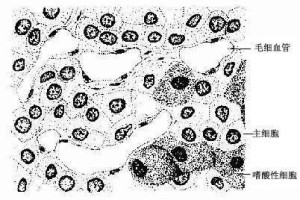

甲状旁腺甲状旁腺甲状旁腺一般有上下两对,位于甲状腺左右叶的背面。成人甲状旁腺呈棕黄色的扁椭圆形,总重约120mg。腺表面包有薄层结组织被膜,腺细胞排列成索团状,其间富含有孔毛细血管及少量结缔组织,还可见散在脂肪细胞,并随年龄增长而增多。

主细胞与嗜酸性细胞主细胞与嗜酸性细胞光镜下,腺细胞可以分为两种:主细胞和嗜酸性细胞。

主细胞(chief cell)

是构成腺实质的主体,呈圆形或多边形,核圆,位于细胞的中央,HE染色切片中胞质着色浅。电镜下,胞质内含粗面内质网、高尔基复合体和直径200~400nm的分泌颗粒,还有一些糖原和脂滴。细胞分泌颗粒内的甲状旁腺激素(parathyroid hormone)以胞吐方式释放入毛细血管内。

嗜酸性细胞

嗜酸性细胞(Oxyphil cell)比主细胞大,核小而固缩,染色较深,数量少,常单个或成群存在于主细胞之间。胞质内含密集的嗜酸性颗粒, 故有强的嗜酸性。电镜下,嗜酸性颗粒乃是线粒体,其它细胞器均不达,糖原和脂滴也少,且无分泌颗粒。人体内这种细胞约在4-7岁开始出现,而在某些动物体内从青春期前后开始出现,随着年龄增长而增多。其功能还不清楚。